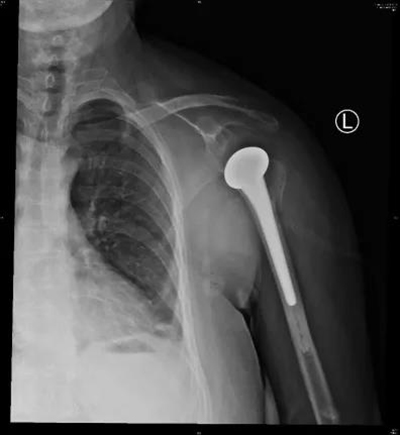

在麻醉手术科医护人员的配合下,创伤中心医师为患者成功实施了“左肩关节半肩置换术”,采用人工假体替代受损的肱骨头,同时进行大小结节固定,肩袖功能重建。术后,患者在科室专业康复师赵闯等的帮助下进行规范功能锻炼,功能恢复顺利,目前已经可以自主完成吃饭、梳头等日常活动。

术中透视及术后X线

患者术后功能恢复良好